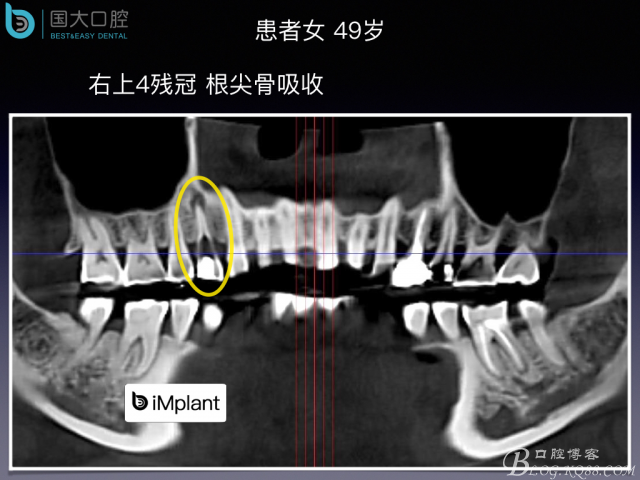

來源于國大口腔 邵現(xiàn)紅醫(yī)生發(fā)表的博文